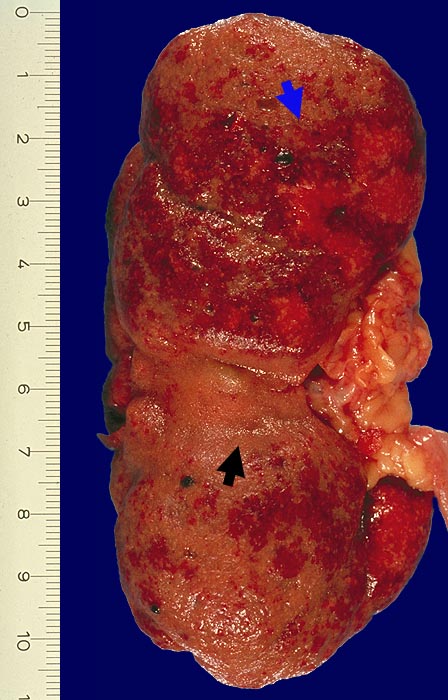

Chronische Pyelonephritis mit akutem Schub

Neben ausgedehnten Narbenfeldern akute Pyelonephritis mit ausgedehnten, konfluierenden Eiterherden umgeben von einem hyperämischen Randsaum.

Chronische Pyelonephritis bei 8% aller Autopsien. 25% der chronischen Pyelonephritiden mit akutem Schub bei Autopsie.